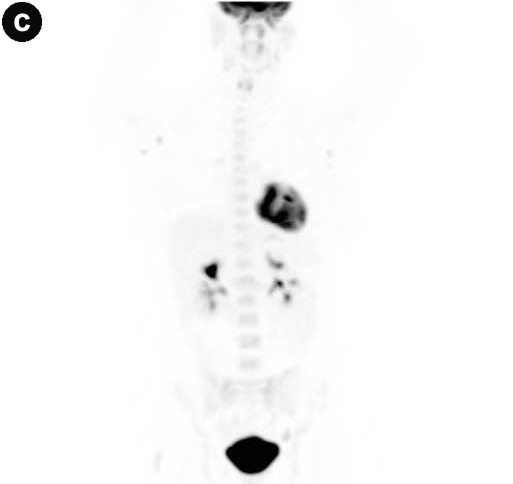

Contrast-enhanced MRI and diffusion-weighted imaging showed: a) an enlarged pancreas associated with highly restricted diffusion and delayed enhancement of the pancreas parenchyma as well as capsule-like peripheral enhancement in the late venous phase; b) main pancreatic duct strictures and chronic pancreatitis changes, suggesting possible autoimmune pancreatitis or a diffuse inflammatory process (Figure 1abc). Multiple mesenteric lymph nodes and two right renal mass-like lesions were also evidenced. 18F-fluorodeoxyglucose positron emission tomography/computed tomography (FDG-PET/CT) showed hypermetabolic activity within all lesions seen on MRI as well as less intense hyperactivity at the level of enlarged bilateral axillary lymph nodes (Figure 1d). These findings raised the hypothesis of lymphoma or tuberculosis. Endoscopic ultrasonography found a diffuse enlarged pancreatic gland and a 40 mm right renal mass. Fine needle aspiration (FNA) was performed both in the pancreas and in the kidney. Cytology showed non-specific inflammatory cells (Figure 2). IgG4-immunostaining was negative, serum IgG4 level was normal and anti-nuclear antibody was negative. Ultrasound-guided percutaneous renal biopsy was inconclusive, revealing a normal renal parenchyma. Cultures (containing a medium specific for mycobacteria and fungus) on FNA and percutaneous renal biopsy specimens were negative.

Figures 1. a. Fusion of axial MRI T2-weighted spin-echo and diffusion-weighted images showing high-intensity focal lesions in the pancreatic head (white arrow) and in the right kidney (black arrow). b. Late venous phase of contrast-enhanced axial MRI T1-weighted gradient-echo image showing a diffusely enhanced and enlarged pancreas with a high intensity capsule-like rim (arrows). c. MRCP image revealing a long segmental stricture (arrow) as well as dilatation and side branch ectasia of the main pancreatic duct. d. FDG-PET/CT showing multiple localizations of intense abnormal radiotracer uptake corresponding to the superior and inferior pole of the right kidney (open arrows), the head and body of the pancreas (closed arrows), and the axillary regions (arrowheads). |

Given the lack of evidence of malignancy or infection, highly active antiretroviral therapy was resumed with a regimen including tenofovir, emtricitabine and boosted darunavir. Two months later, the patient was totally asymptomatic. She had had an undetectable HIV viral load. Lipase and CRP were within the normal range, and abnormal findings on MRI and FDG-PET/CT had totally disappeared at the level of the pancreas and were almost entirely normalized in the other sites (Figure 3).

Figure 3. Image following highly active antiretroviral therapy. a. Fusion of axial MRI T2-weighted spin-echo and diffusion-weighted images showing complete resolution of the pancreatic lesions and dramatic regression of the right kidney lesion. b. Axial MRCP showing improvement of the main pancreatic duct abnormalities. c. FDG-PET/CT revealing slight residual radiotracer uptake in the axillary lymph nodes. |